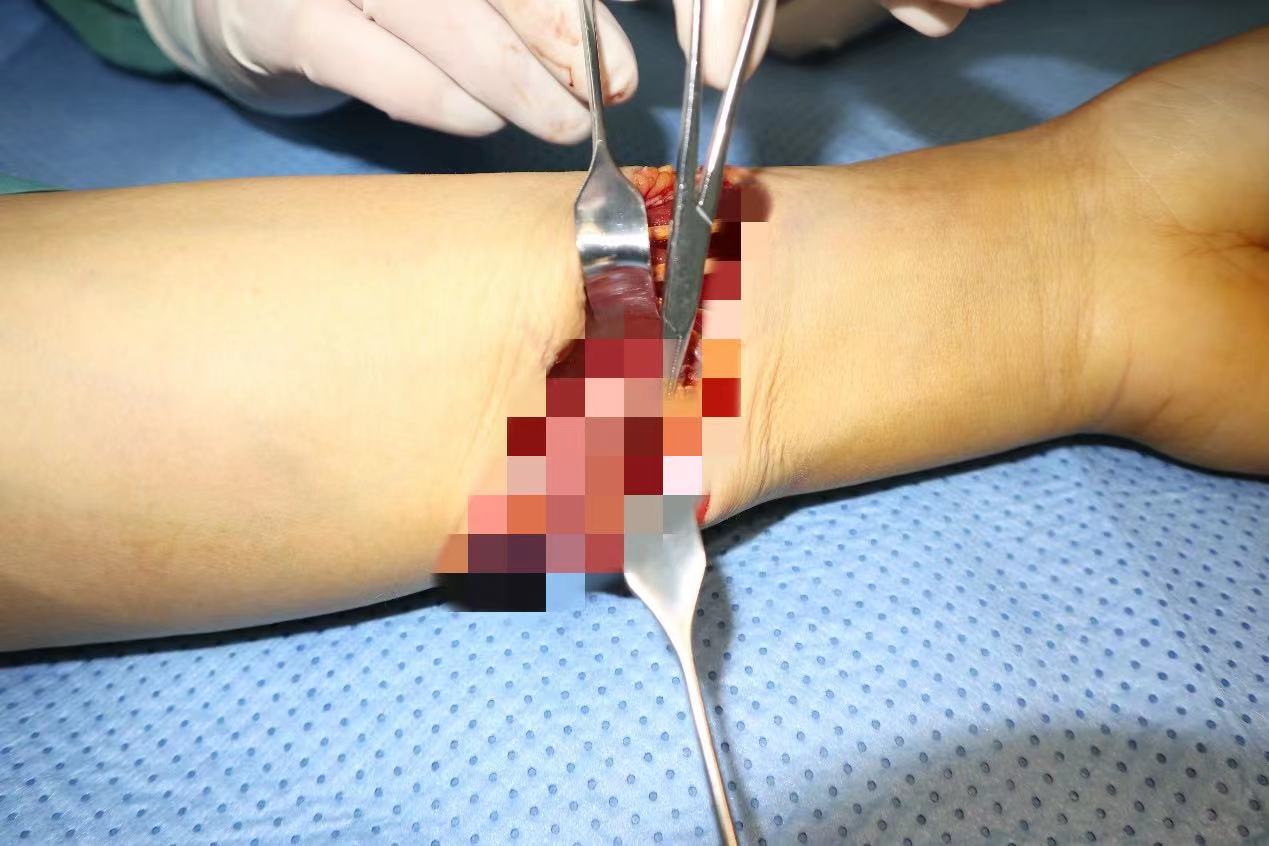

裴艳涛立即将患者情况向科室主任汇报。手足外科主任朱磊、副主任许庆家指示手足外科团队做好术前准备,尽快手术。裴艳涛立即联系手术室护士长翟永华给予协调,在最短的时间内安排护士准备手术,麻醉师刘宛灵负责麻醉,许庆家、裴艳涛、王俊涛主治医师为患者进行手术。

钢筋被顺利取出,专家团队对伤口进行仔细清创,探查见:尺动脉断裂,尺神经部分断裂并严重挫伤,2—5指指浅屈肌腱断裂,桡侧腕屈肌腱、尺侧腕屈肌腱部分断裂,随后在显微镜下再次清创,显微镜下吻合尺动脉、修复尺神经,对损伤的肌肉及肌腱给予缝合,手术顺利,患者安返病房。